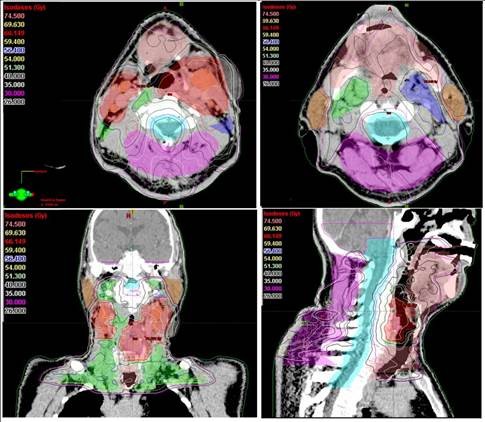

Son yıllarda yapay zeka uygulamalarının kanser alanında kullanılması için yapılan araştırmalarda artış olduğunu anlatan Prof. Dr. Yavuz, "Tümör ve çevredeki normal dokuların üç boyutlu olarak sınırlarının çizildiği bu süreç, bir hastanın tümör bölgesine ne kadar radyasyon alacağını ve ışının en uygun nasıl odaklanacağını belirler. Özellikle ABD'nin Ulusal Sağlık Enstitüsü tarafından da desteklenen önemli bir araştırma projesinde yapay zeka kullanarak yüksek riskli tümör hedef hacimlerinin sınırlarının 3 boyutlu olarak belirlenmesi için her bir görüntüleme film kesitinde tümör ve normal doku sınırlarının tek tek çizilmesi işlemlerini otomatikleştirmek için yeni bir yöntem geliştirildi" dedi.

"Bir sonraki aşamada, eldeki tüm veriler birleştirilerek, orta ve düşük riskli tümör bölgelerinin de otomatik ve en doğru bir şekilde belirlenmesi mümkün olabileceği gibi, hastaya özgü en uygun radyoterapi veya kemoterapiyi de ayarlamak adına çeşitli genetik mutasyonlara ait bilgiler de bu yapay zeka uygulamasına entegre edilebilecektir. Bu şekilde, kanser tedavisi sonuçlarında başarı oranlarının artması da kaçınılmazdır. Yöntemin çok önemli bir avantajı da bizlere sunduğu yüksek hız ve verimliliktir. Normalde, örneğin bir baş boyun kanserinde, hedeflenen hacimleri belirlemek bir hekimin 1-4 saatini alır. Yapay zeka kullanan özel bilgisayar sistemiyle hem 1 dakikadan kısa bir sürede hedef hacimler belirlenebilmekte, hem de hekimden hekime değişebilen hata payları ihtimali tümüyle ortadan kalkmaktadır."